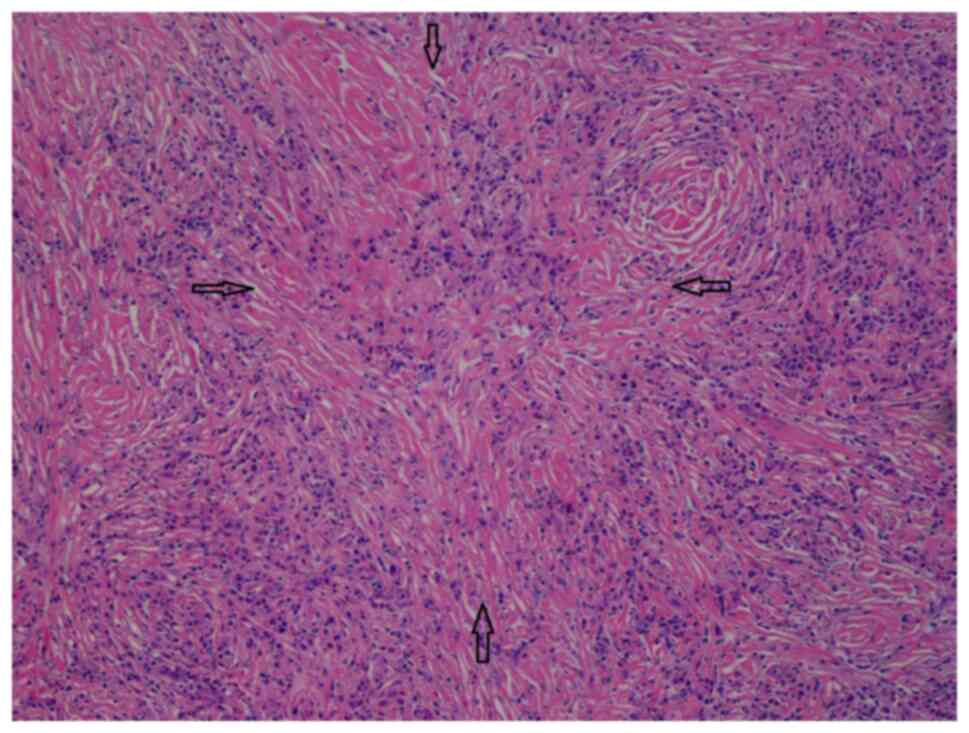

In view of the diagnostic uncertainty, a left-sided submandibular sialoadenectomy with lymph node excision was performed by the surgeons. A histological examination of the left salivary glandular tissue (hematoxylin and eosin staining; performed by the Histopathology Laboratory of Yan Chai Hospital, Hong Kong, SAR, China; x100 magnification) revealed evidence of chronic sclerosing sialadenitis (Fig. 4). The salivary gland lobules were mostly replaced by storiform fibrosis, reactive lymphoid hyperplasia and lymphoplasmacytic infiltration. Plasma cells were abundant. Obliterative phlebitis was not observed. There was no evidence of malignancy. Immunohistochemistry performed by the Histopathology Laboratory of Yan Chai Hospital revealed a high number of IgG4 plasma cells >100/HPF in the most affected area and the IgG4:IgG plasma cell ratio was >40% (the images for this were not available). All these features were in-keeping with IgG4-RD. Similar features were also observed in the sampled submandibular lymph node.

Figure 4

Histopathological slide (hematoxylin and eosin staining, x100 magnification) of the left salivary glandular tissue showed storiform fibrosis, a feature of IgG4-RD.